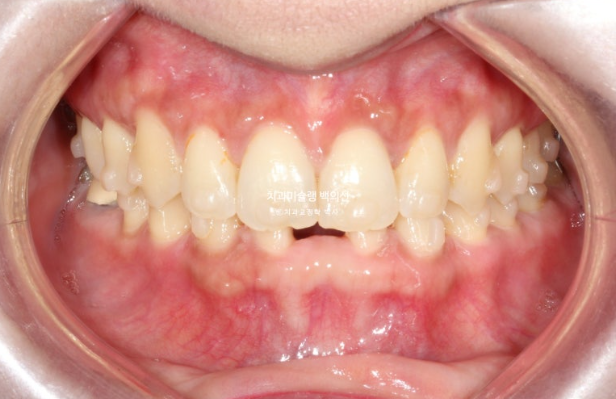

교정치료를 위해 내원한 환자분입니다. 아래 앞니 두 개가 없어서 이 사이 벌어짐을 치료하고자 오셨습니다.

윗니가 아랫니를 깊게 덮는 과개교합도 보입니다.

송곳니가 없는 것 처럼 보이지만 사실은 앞니 2개가 선천적으로 없는 상태입니다.